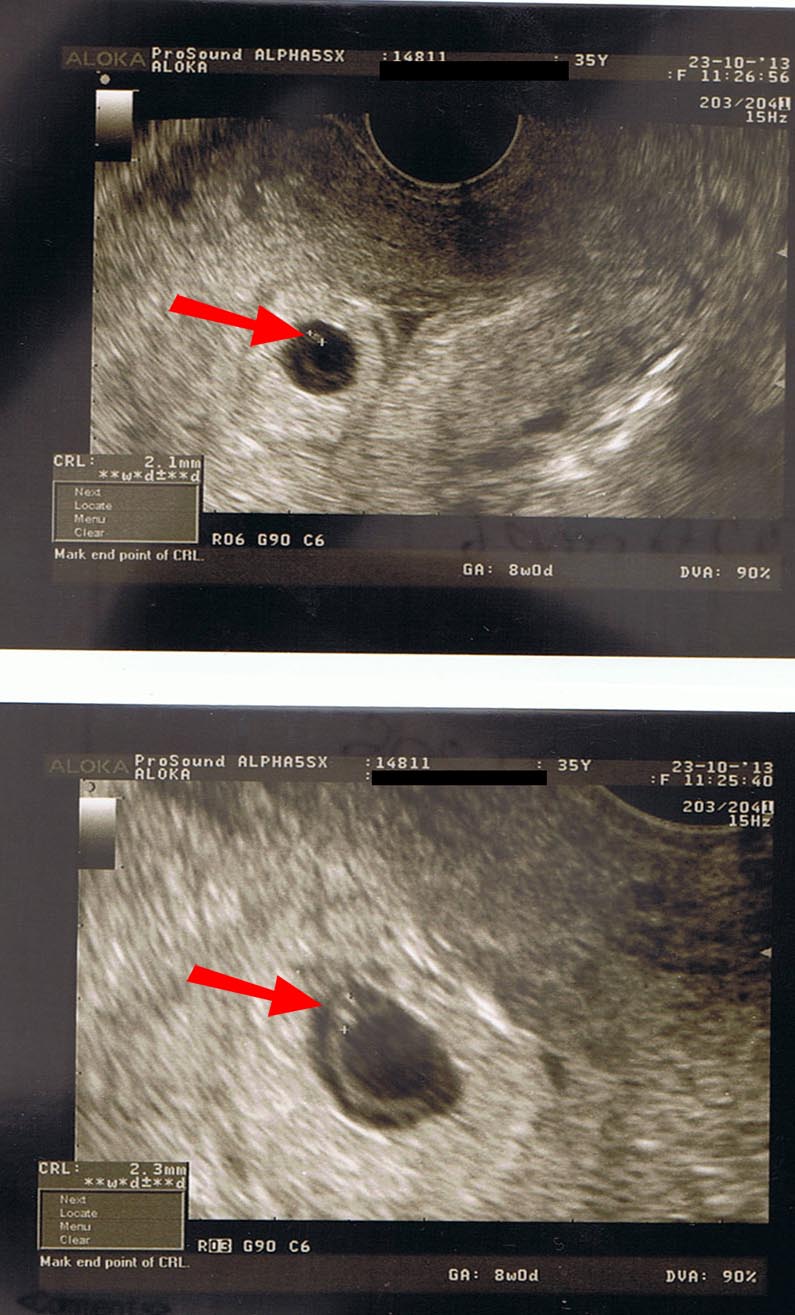

Trois échographies de dépistage sont recommandées aux femmes enceintes à chaque trimestre de la grossesse. Dans le cas d’une grossesse intra utérine d’évolution incertaine (sac gestationnel intra-utérin < 25 mm) sans vésicule vitelline visible, l’absence d’apparition d’un embryon avec une activité cardiaque à l’échographie endovaginale dans un délai d’au moins 14 jours permet d’affirmer que la grossesse est arrêtée (Grade C). Il mesure alors 2 à 3 mm.L'utilisation de la voie endovaginale est souvent nécessaire pour le voir.

Une grossesse gémellaire arrêtée à 7.5 SA (hiver 11), deuxième +++ suite à IAC4 :. Plus de sujets relatifs à :. Bonjour, j’ai fait une échographie hier, le choc, embryon de 3mm alors que je devais être à 8SA.

C'est parce que le fœtus a déjà été suffisamment formé. Parfois, ça se joue au jour près. Bien qu'au début de la sixième semaine de grossesse l'embryon soit encore très petit (il mesure environ 2-4 mm), il commence à subir de grands changements et à augmenter rapidement sa taille.A la fin de cette semaine, il mesurera environ 5-6 mm et pourra être vu à l'échographie.